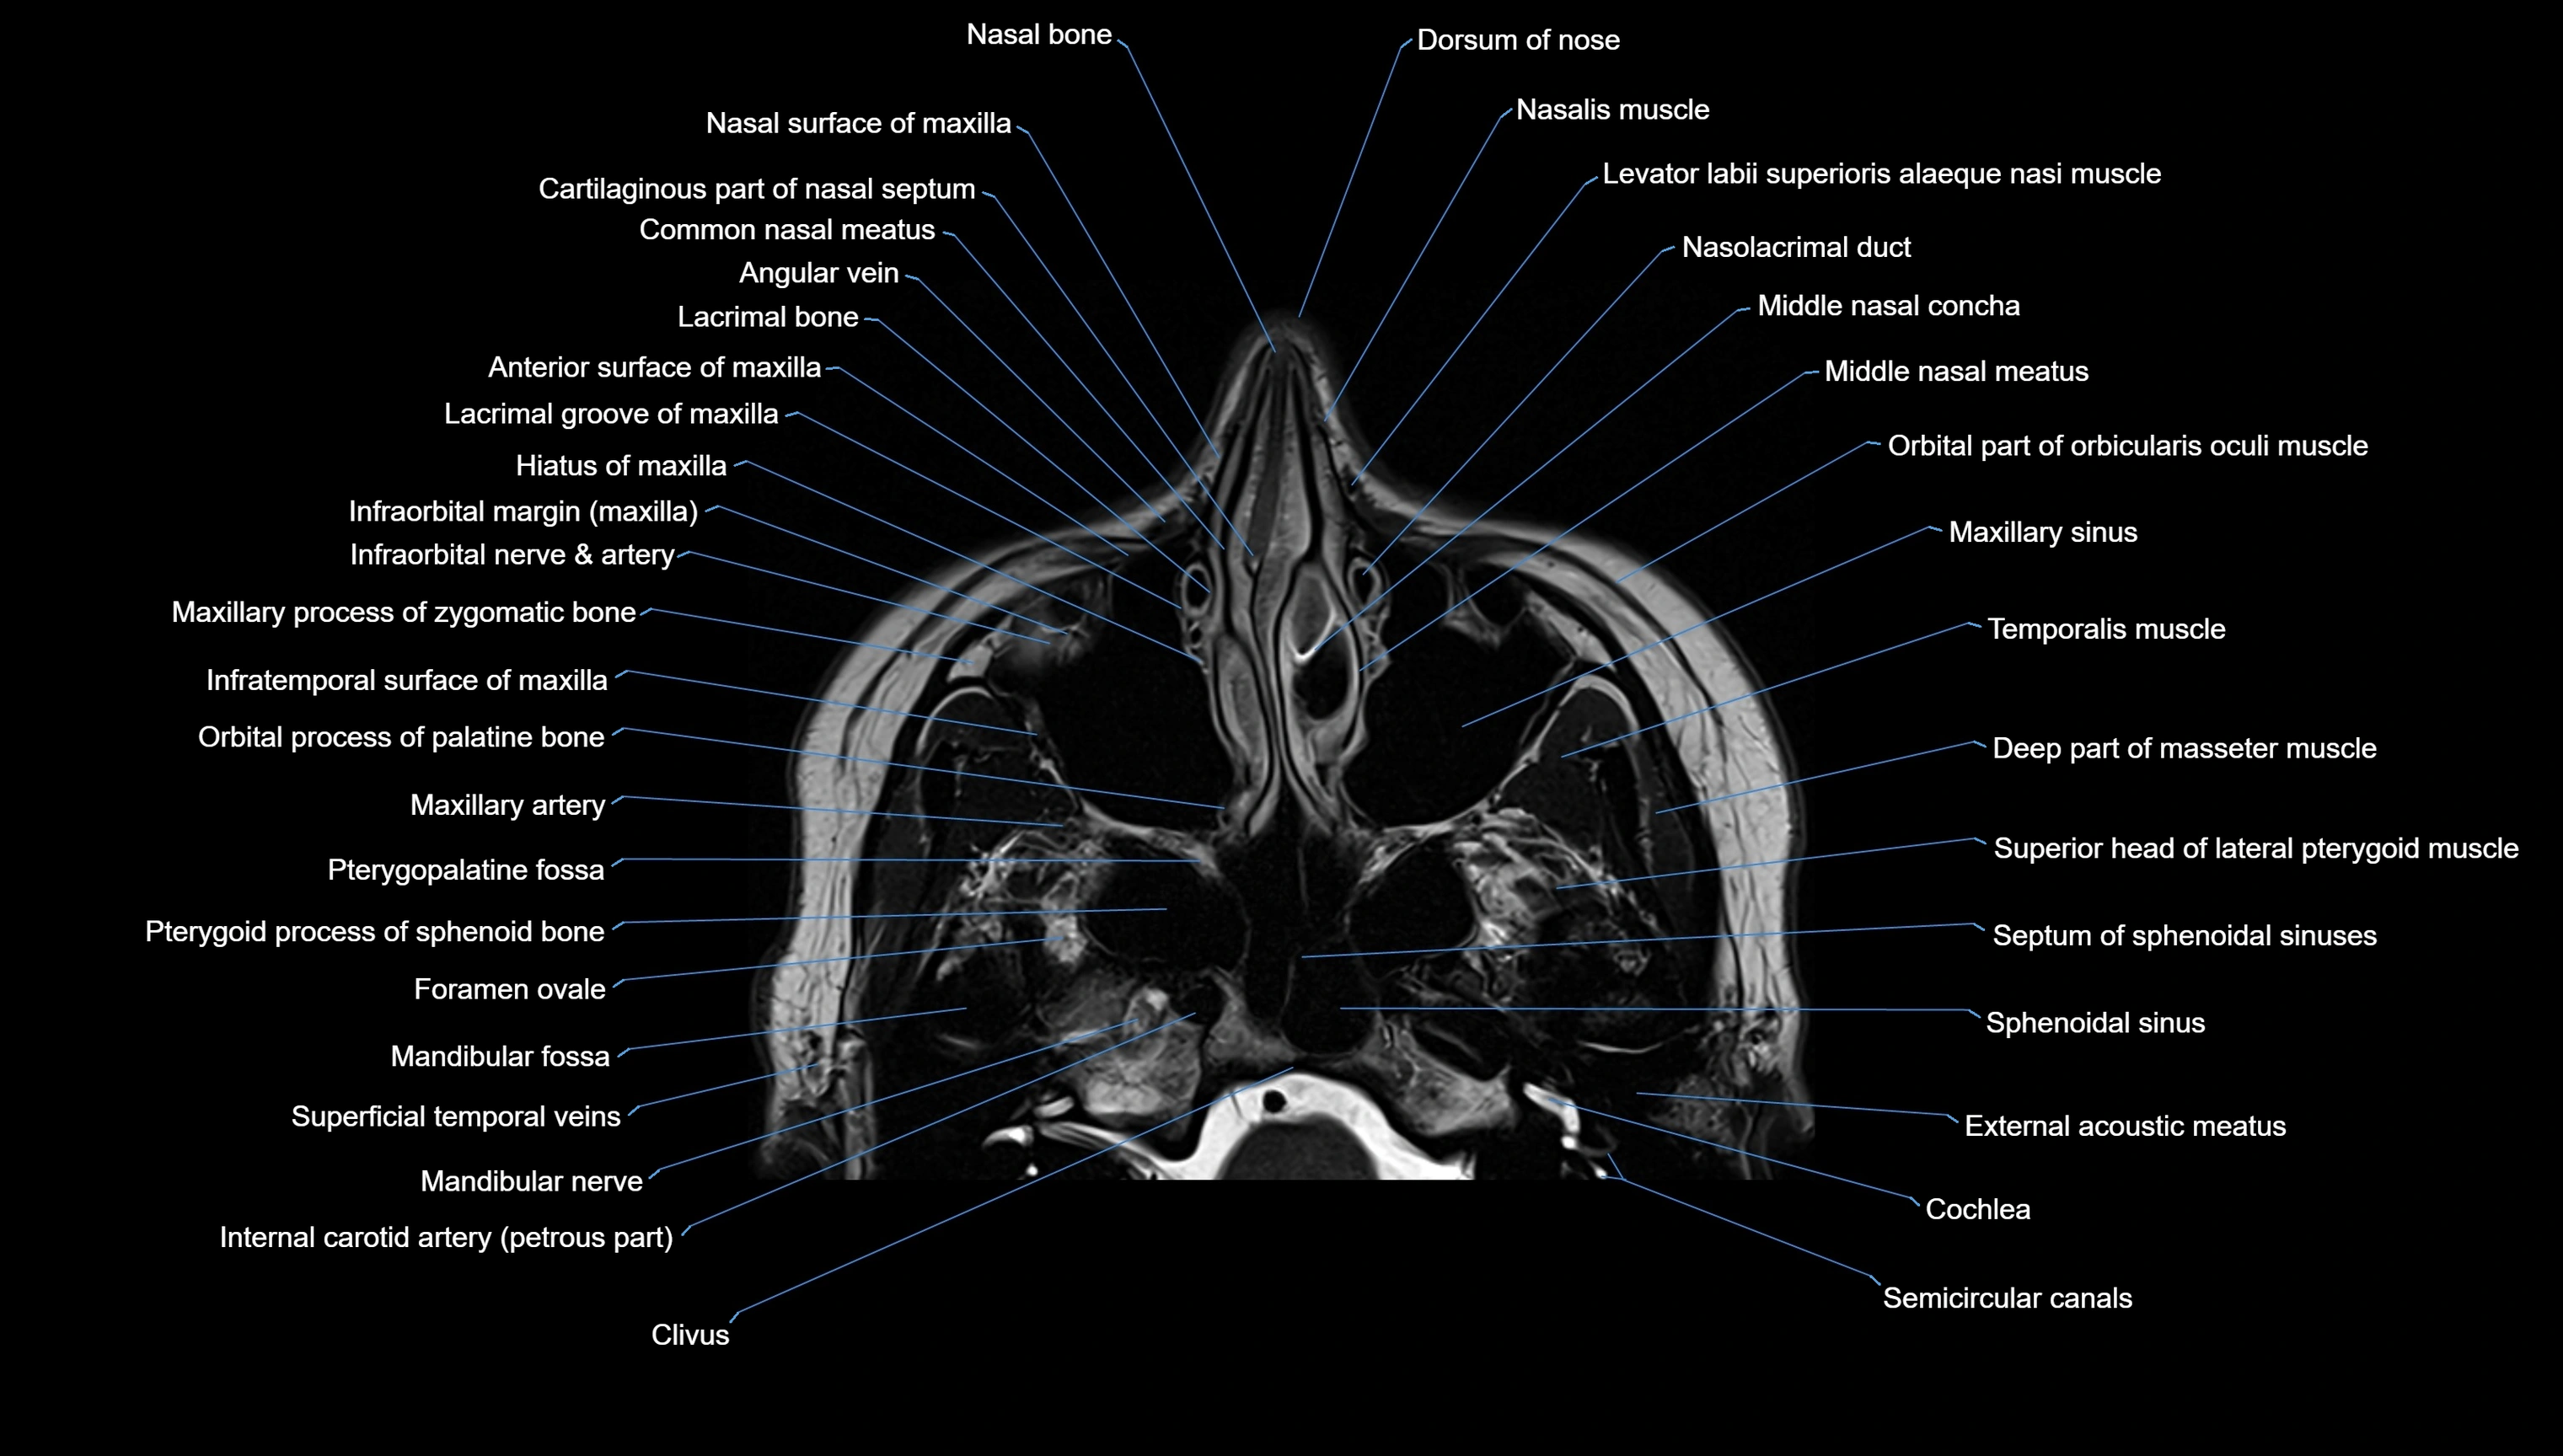

MRI images